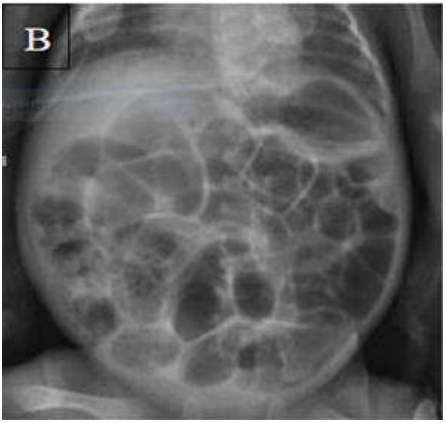

Uma recém-nascida (RN) pré-termo, com 28 semanas de idade gestacional, aos seis dias de vida, inicia quadro de instabilidade térmica, hipoatividade, apneia, resíduo gástrico aumentado, diminuição da perfusão periférica, distensão abdominal, ausência dos ruídos hidroaéreos e enterorragia. Verificam-se SatO2 = 92%, FC = 120 bpm e FR = 65 irpm. Ela é filha de pais saudáveis, não consanguíneos, com sorologias maternas sem alterações. O parto ocorreu por cesariana, com um índice de Apgar ao 1º e 5ºminuto de 7 e 8 respectivamente (PN = 1.055 g; comp = 36 cm; PC = 28,5 cm). Teve a primeira eliminação de mecônio nas primeiras 24 horas de vida. O resultado de exames laboratoriais evidenciou leucopenia, neutropenia, queda aguda do hematócrito e trombocitopenia. A imagem do exame radiológico encontra-se a seguir.